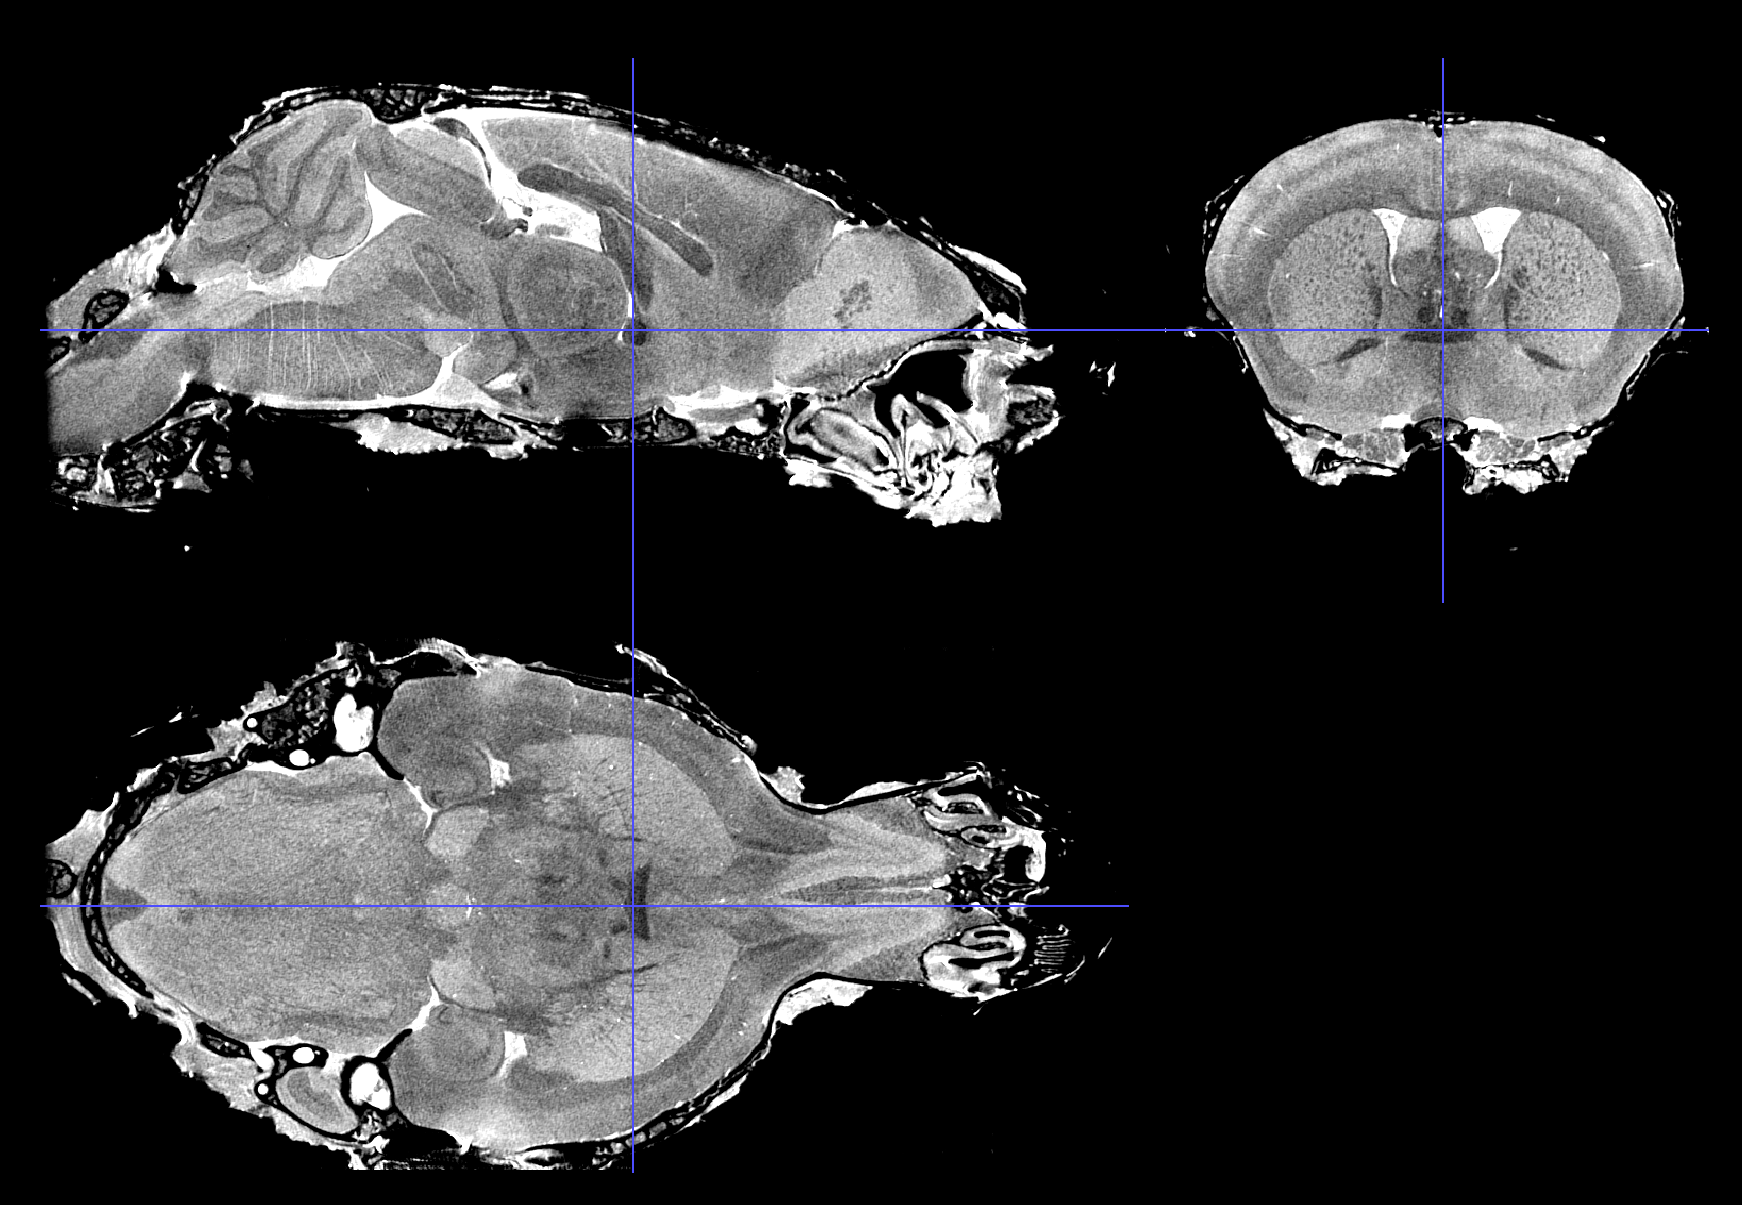

Scalable Brain Atlas  Coronal3d

Mouse - Allen Mouse Brain Common Coordinate Framework version 3

1. Lein ES, Hawrylycz MJ, Ao N, et al. (2007) "Genome-wide atlas of gene expression in the adult mouse brain." Nature 445(7124):168-76. [doi 10.1038/nature05453]